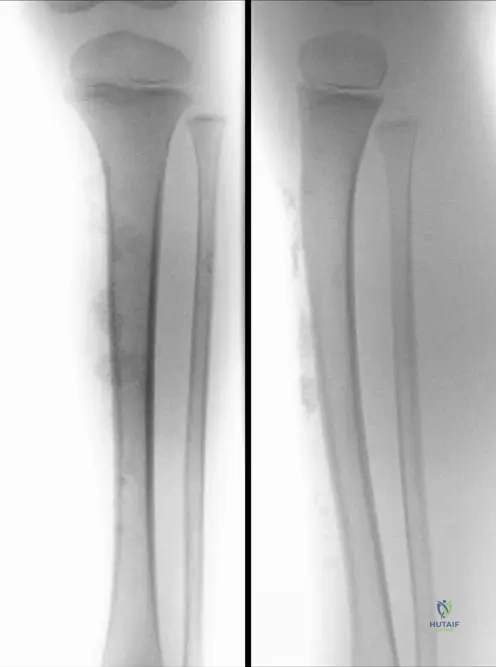

A 6-year-old boy presents with a painful limp. Radiographs of his foot, shown in Fig. 13.23 a and b, demonstrate fragmentation of the navicular bone. What is the most likely pathophysiological mechanism leading to these findings?

View Answer & Explanation

Correct Answer: C

Rationale: The text states that the navicular bone might be compressed between the already ossified talus and cuneiforms, especially when the child becomes heavier. This compression involves the vessels in the central spongy bone, leading to ischemia, which is the underlying cause of avascular necrosis and subsequent fragmentation. While trauma can occur, the primary mechanism described for Köhler's disease is compression-induced ischemia, not a direct traumatic fracture. Chronic inflammation, congenital malformation, or systemic metabolic disease are not the described pathophysiology.

A 6-year-old boy presents with a painful limp and tenderness over the medial aspect of his foot. Radiographs show fragmentation of the navicular bone. Seven years later, at age 13, follow-up radiographs (Fig. 13.23c) demonstrate a complete rebuilding of the navicular bone. This long-term finding indicates which of the following about Köhler's disease I?

Rationale: The demonstration of "a complete rebuilding of the navicular bone" seven years later strongly indicates that Köhler's disease I is a self-limiting condition with a favorable prognosis, often resolving without aggressive intervention. It is not progressive, degenerative, or typically associated with long-term impairment or infection. The text does not mention surgical intervention as a typical requirement.

A 6-year-old boy presents with a painful limp. Radiographs of his foot (Fig. 13.23 a and b) show fragmentation of the navicular bone. Which of the following is the most characteristic radiographic finding in the acute phase of Köhler's disease I?

Rationale: The clinical context for Fig. 13.23 explicitly states, "Note the fragmentation of navicular bone on right side, especially in lateral view." This fragmentation, often accompanied by sclerosis (increased density), is the hallmark radiographic finding of avascular necrosis of the navicular in Köhler's disease I. While there might be some density changes, fragmentation is the most characteristic feature. The other options describe findings not typical of Köhler's disease I.

A 6-year-old boy presents with a painful limp and tenderness over the medial aspect of his foot. Radiographs (Fig. 13.23 a and b) show fragmentation of the navicular bone. Which view is specifically highlighted as demonstrating the fragmentation well?

Rationale: The clinical context for Fig. 13.23 states, "Note the fragmentation of navicular bone on right side, especially in lateral view." While fragmentation may be visible on AP views, the lateral view is specifically mentioned as being particularly good for demonstrating this characteristic finding. The other views are not highlighted for this specific purpose in the provided text.